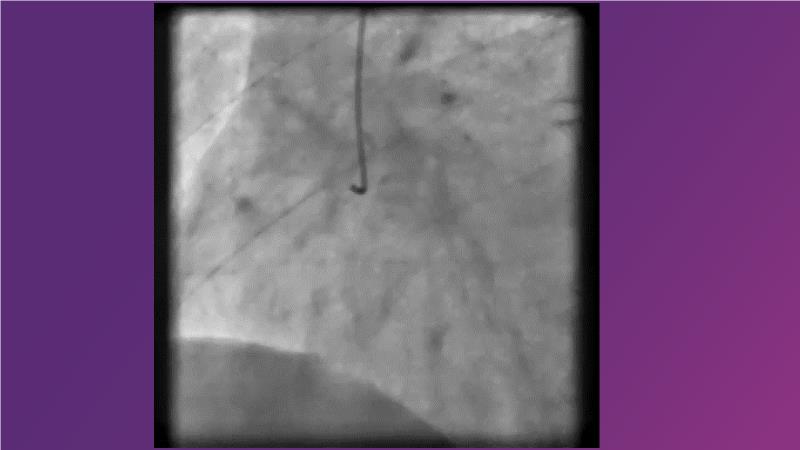

DES and DCB, can these two technologies be complementary for the treatment of the same patient? What are the advantages and how to proceed? You will know everything by watching this presentation based on concrete cases.